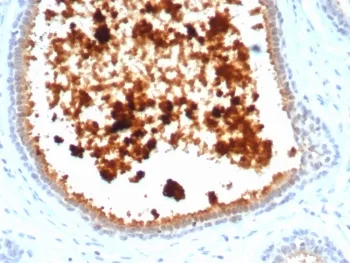

Mammaglobin A Recombinant Antibody / SCGB2A2

Mammaglobin, 10 kDa, is a cytoplasmic protein, a mammary-specific member of the uteroglobin family. It is related to a family of epithelial secretory proteins that includes prostatein and Clara cell protein. Mammaglobin occurs in about 80% of breast carcinomas. The extend is generally larger than that of GCDFP-15. Up to 15% of non-breast carcinomas (such as stomach, lung, colon, hepatobiliary, thyroid, ovarian, and urothelial carcinomas) have been reported positive, usually only focally. Mammaglobin is a sensitive and fairly specific marker for breast carcinoma.UniProt:

IHC-PFormat: